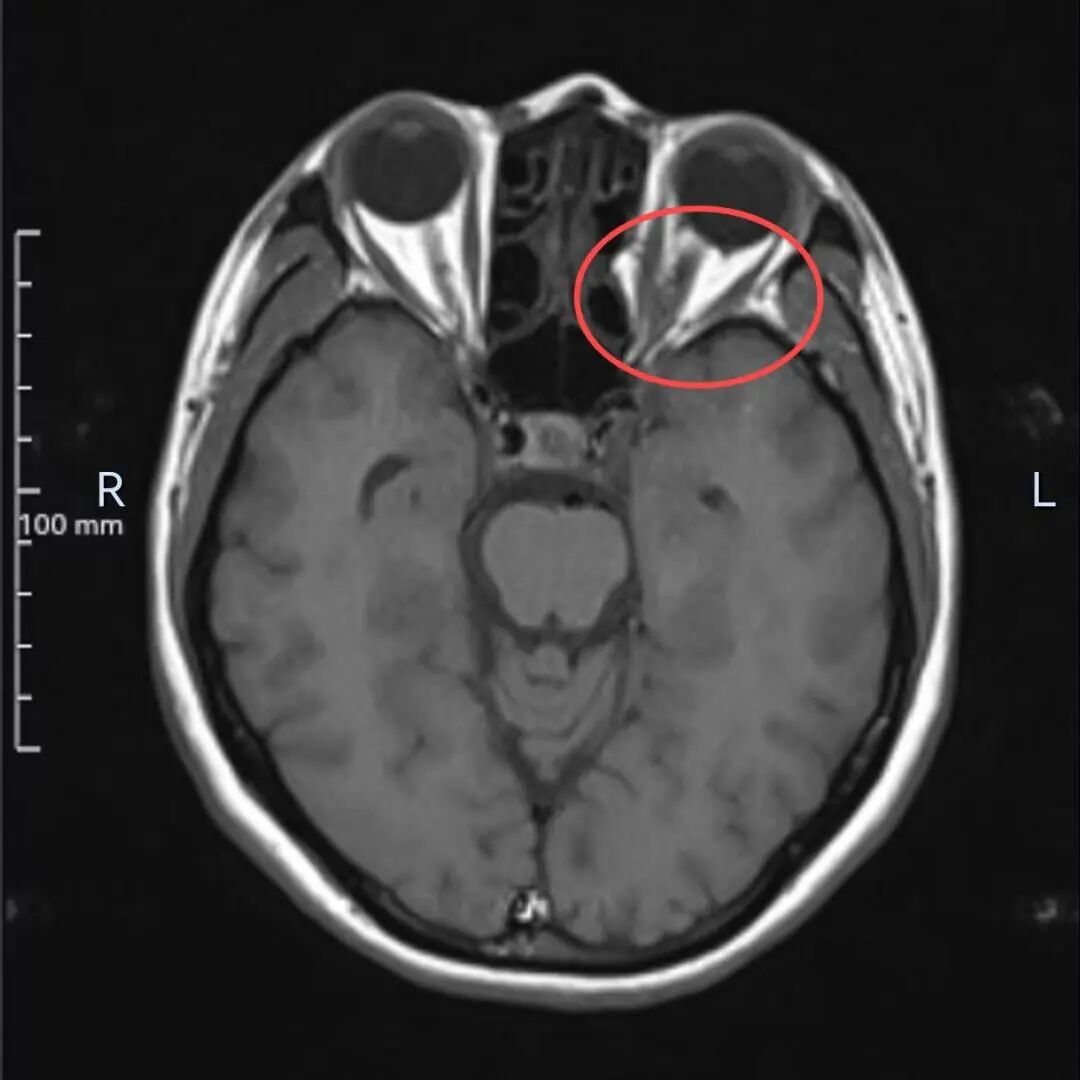

多年来,贵州航天医院各科室紧跟医学前沿,不断强技术、补短板,大力开展新技术、新项目,完成了许多高精尖、高难度、本地区“首例”的技术,填补了医院医疗技术空白,满足了群众日益增长的医疗需求。 案例分享 患者在两年前无明显诱因出现左眼胀痛、左眼视力下降等症状,由于当时患者自感不太严重,未予重视,随着时间的推移,症状逐渐加重,遂前来我院就诊,为更好的为患者进行诊治,收入了耳鼻喉科。经眼科查体显示:VOD(矫正视力)→1.0,VOS(矫正视力)→1.0,进行眼眶平扫+MRI检查后,初步诊断为:左眼球后脂肪间隙内占位,考虑良性病变,血管瘤可能。 考虑到患者病情复杂,耳鼻喉科组织眼科、麻醉科等科室开展了多学科联合会诊,对患者病情、既往病史等进行了全面深入的综合分析研讨,制定了鼻内镜下左侧鼻窦功能开放术+左侧眶内肿瘤切除术的方案,由于手术难度较大,在充分告知手术风险及并发症等相关信息后,患者及家属同意手术。经过充分的术前准备,耳鼻喉科借助经鼻内镜,成功通过鼻窦经由筛窦眶纸板、蝶窦外侧壁将肿瘤完整切除,最大程度地保护了眶内的血管、神经等重要组织。 术后,患者未出现视力减退、视野缺损等并发症,仅眶周稍青紫肿胀和轻微复视。患者2周后复查,复视症状、眶周青紫肿胀消除,术后MRI(眼眶平扫+增强扫描)显示左眶内肿物已消失。 该技术的开展,特别邀请了中山大学附属第一医院耳鼻喉科专家左可军教授莅临主刀,并对该技术的实施进行指导,已成功完成多例鼻眼相关内镜手术,解决了患者外出就医难、排队时间长、花费多等难题,让广大民众在家门口享受到了优质的医疗服务资源。 什么是鼻内镜下经鼻腔、 鼻窦进路眶内肿物切除术 眼眶是一个狭小的解剖间隙,结构复杂,功能重要,周围临近组织较多,含有许多重要结构,眶深部的肿瘤切除手术难度大,容易侵犯神经,出现视力丧失等并发症。随着眼-鼻相关学科发展和微创理念的深入,鼻内镜内侧开眶入路得到显著发展和应用,鼻内镜下经鼻腔、鼻窦进路眶内肿物切除术,具有微创、直视、并发症少等优势,目前已成为眶内肿物切除首选手术进路,主要应用于泪道系统疾病、眶骨折修复、眼眶内侧肿瘤切除、眼眶减压、海绵状血管瘤切除等。 鼻内镜下经鼻腔、鼻窦 进路眶内肿物切除术原理 手术基于先进的鼻内镜设备,通过鼻腔入路直接对眼眶及其毗邻区域进行操作,鼻腔与眼眶相邻,眼眶内侧壁主要由筛骨纸板构成,骨质菲薄,很容易经此进入眼眶,所以鼻腔可作为合适的手术通道,让操作更精准、更微创,同时,内镜下经鼻眼眶手术可利用该通道实现面部无切口。 鼻内镜下经鼻腔、鼻窦 进路眶内肿物切除术优势 ✔肿物可完整切除,较好的保护视力。 ✔可避免眼外部入路及经颅开眶入路的头面部切口。 ✔无脑组织的牵拉损伤,对眼内容物的牵拉损伤较小。 ✔经鼻切口外形无改变,术中组织结构放大、视野清晰,肿物分离更便捷。 贵州航天医院耳鼻喉科专家团队 左可军 中山大学 附属第一医院耳鼻咽喉科 贵州航天医院耳鼻喉科 特聘教授 医学博士 硕导 主任医师 临床擅长:鼻科、鼻眼相关外科、鼻颅底相关外科以及鼻变态反应科的临床和基础工作。 南方青年鼻科联盟创始人,担任中国医师协会耳鼻咽喉科分会整形美容学组委员、海峡两岸医药卫生交流协会眼科学专业委员会眼科内窥镜微创手术学组委员、广东省精准医学应用学会头颈肿瘤分会副主委、广东省中西医结合学会耳鼻咽喉科分会副主委、广东省眼健康协会眼与全身疾病专业委员会常委。获得国家二级运动员和南粤优秀研究生称号,2018年荣获“广东医院最强科室之实力中青年医生”,2020年荣获全国卫生健康系统抗疫先进集体、中国医师协会耳鼻咽喉头颈外科分会抗疫先进个人,2021年荣获广东省科技进步一等奖,2023年荣获第七届“羊城好医师”。 张光进 耳鼻喉科主任 副主任医师 临床擅长:对耳鼻喉头颈常见病的诊治具有丰富的临床经验,擅长鼻内镜、耳内镜、耳显微、头颈咽喉部肿瘤及眩晕手法复位等的诊疗。 曾先后前往第三军医大学西南医院、复旦大学耳鼻喉科医院、上海新华医院及北京友谊医院进修学习;遵义市医学会常务委员;主持及参与级科研课题2项,发表专业论文10余篇。 陈维信 耳鼻喉科 主任医师 临床擅长:对耳鼻喉科常见疾病的诊治具有丰富的临床经验,擅长耳、鼻、喉及头颈部位的手术。 曾先后前往上海交通大学附属仁济医院耳鼻喉-头颈外科、北京大学人民医院耳鼻喉-头颈外科参加鼻内镜外科进修学习。中国睡眠研究会委员,贵州省医学会耳鼻喉-头颈外科学分会委员,贵州省耳鼻喉-头颈外科学会理事,贵州省医学会变态反应学分会委员,贵州省防聋治聋技术指导组专家,遵义市耳鼻喉科分会副主任委员,遵义市医疗事故鉴定专家库成员;主持省部级科研课题2项,发表专业论文20余篇。 秦 晋 耳鼻喉科 副主任医师 临床擅长:对耳鼻喉科常见疾病的诊治具有丰富的临床经验,擅长耳、鼻、喉及头颈部位的手术。 遵义市医学会常务委员;曾先后在第三军医大学西南医院、湖南湘雅鼻颅底培训班进修学习。 贵州航天医院耳鼻喉科简介 基本情况 贵州航天医院耳鼻喉科拥有一支经验丰富、技术精湛的医疗团队,共有医师9名,其中副高级以上专家5名,医学硕士2名,开放床位20张,拥有德国WOLF鼻窦内窥镜系统、日本奥林巴斯电子喉镜、奥林巴斯电子鼻咽镜、丹麦临床听力监测设备、声导抗仪、听觉诱发电位、耳声发射仪、美国杰西低温等离子治疗仪、杭州好克鼻窦内窥镜系统、鼻动力系统、耳显微镜、耳用电钻、微波治疗仪等先进设备。 专科特色 (一)耳部疾病 耳内镜下胆脂瘤切除术、III型鼓室成形术+人工听骨听骨链重建术。 (二)鼻部疾病 内镜下鼻息肉切除术、鼻窦功能开放术。 (三)咽喉疾病 内镜下扁桃体、腺样体低温等离子切除术。 (四)交叉学科 1.经鼻内镜下眶内肿瘤切除术 2.经鼻内镜下鼻腔泪囊吻合术 诊疗范围 (一)常见耳疾的诊断和治疗:中耳炎、耳聋、耳鸣等。通过各种耳科检查手段,如耳镜检查、听力测试和耳脑干听觉诱发电位检查等,准确诊断患者病情,制定个性化治疗方案。 (二)鼻炎、鼻窦炎、鼻出血等鼻科疾病的诊断和治疗:采用微创技术,如鼻内窥镜检查、低温等离子手术等,为患者提供有效的治疗方案。 (三)喉炎、声带息肉、声带白斑等喉科疾病的诊断和治疗:通过声带电子镜、喉镜等设备,准确判断患者的喉部病变,为患者提供精准的治疗方案。 (四)鼻眼、鼻颅底相关手术。